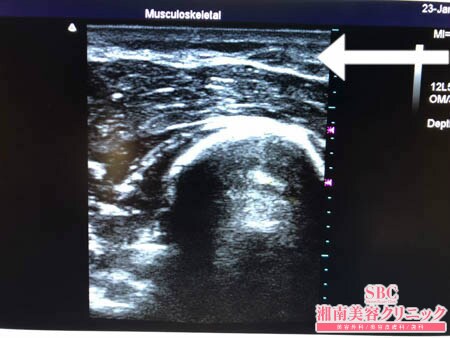

No.208684【脂肪吸引】【動画あり】湘南美容外科脂肪吸引最高責任者である竹田先生による脂肪吸引のフォトギャラリー!茨城からご来院!ストレスで10kg太ってしまい脂肪吸引で確実に細くする!二の腕の脂肪吸引!3Dタッチビュー・左二の腕

今回は二の腕の脂肪吸引の

術中の模様を紹介しましょう。